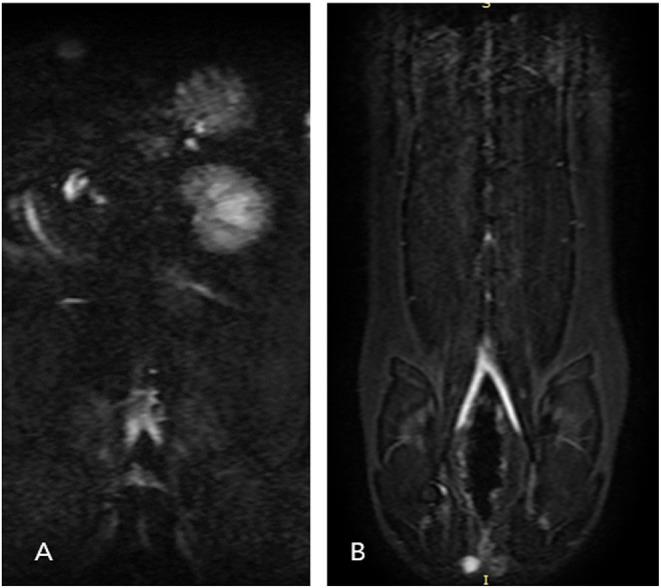

Arterial thromboembolism is associated with high morbidity and mortality rates in cats. Definitive diagnosis requires advanced imaging modalities, such as computed tomography angiography (CTA) and contrast-enhanced (CE) magnetic resonance angiography (MRA). However, CTA involves exposure to a large amount of ionized radiation, and CE-MRA can cause systemic nephrogenic fibrosis. Non-contrast-enhanced (NE) MRA can help accurately diagnose vascular lesions without such limitations. In this study, we evaluated the ability of NE-MRA using three-dimensional electrocardiograph-gated fast spin-echo (3D ECG-FSE) and 3D time-of-flight (3D TOF) imaging to visualize the aorta and external iliac arteries in clinically healthy cats and compared the results with those obtained using CE-MRA. All 11 cats underwent 3D ECG-FSE, 3D TOF, and CE-MRA sequences. Relative signal intensity (rSI) for quantitative image analysis and image quality scores (IQS) for qualitative image analysis were assessed; the rSI values based on the 3D TOF evaluations were significantly lower than those obtained using 3D ECG-FSE (aorta 3D TOF: 0.57 ± 0.06, aorta 3D ECG-FSE: 0.83 ± 0.06, < 0.001; external iliac arteries 3D TOF: 0.45 ± 0.06, external iliac arteries 3D ECG-FSE:0.80 ± 0.05, < 0.001) and similar to those obtained using CE-MRA (aorta: 0.58 ± 0.05, external iliac arteries: 0.57 ± 0.03). Moreover, IQS obtained using 3D TOF were significantly higher than those obtained using 3D ECG-FSE (aorta 3D TOF: 3.95 ± 0.15, aorta 3D ECG-FSE: 2.32 ± 0.60, < 0.001; external iliac arteries 3D ECG-FSE: 3.98 ± 0.08, external iliac arteries 3D ECG-FSE: 2.23 ± 0.56, < 0.001) and similar to those obtained using CE-MRA (aorta: 3.61 ± 0.41, external iliac arteries: 3.57 ± 0.41). Thus, 3D TOF is more suitable and produces consistent image quality for visualizing the aorta and external iliac arteries in clinically healthy cats and this will be of great help in the diagnosis of FATE.